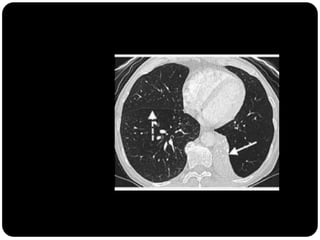

Atelectasia

 Diminuição de volume do segmento, deslocamento de uma ou mais

fissuras interlobares em direção à parte atelectasiada, desvio do mediastino

para o lado envolvido, deslocamento hilar, estreitamento dos espaços

intercostais e hiperinsuflação dos outros lobos / segmentos não atelectasiados

de forma compensatória.

 Obstrução de brônquio por carcinoma

broncogênico sempre deve ser considerada

em adulto com atelectasia lobar;

 Nas crianças: mais comum aspiração por

CE;